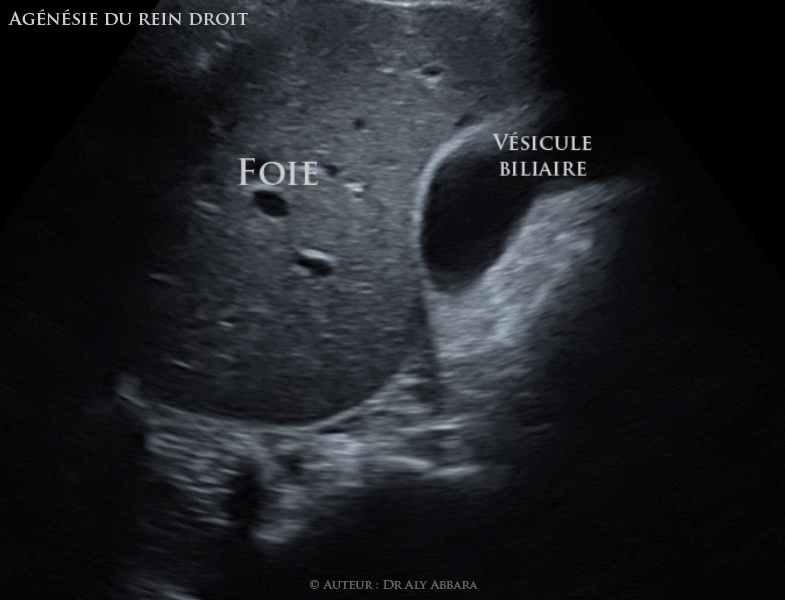

Agénésie du rein droit associée à une malformation utérine de type d'utérus bicorne unicervical

Séquences Vidéo et images échographiques mettant en évidence une agénésie rénale unilatérale droite associée à un utérus malformé de type "utérus bicorne unicervical".

Par définition, l'espace de Morisson (ou l'espace interhépatorénal droit) n'existe pas en raison de l'absence du rein droit.

Il s'agit d'une femme âgée de 32 ans chez laquelle ce complexe malformatif a été diagnostiqué auparavant suite à la découverte de la malformation utérine au cours de sa première grossesse.